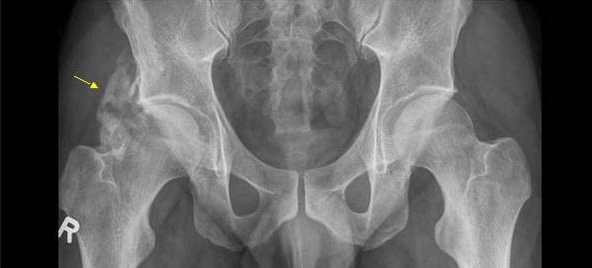

Đây là loại xương có tổ chức cao, giống hệt với xương trong khung xương bình thường của bạn, được hình thành một cách bất thường lệch vị trí trong các mô mềm. Trên phim X-quang, khối xương non này có thể có hình ảnh “giống như bắp rang bơ”. Ở giai đoạn trưởng thành, khối xương này có cấu trúc vi thể phức tạp, thể hiện qua “hiện tượng phân vùng” (zonal phenomenon) đặc trưng—với lõi trung tâm là các tế bào sợi, vùng giữa là các tế bào tạo xương và lớp vỏ ngoài cùng là xương trưởng thành. Tác động của việc này vô cùng nghiêm trọng. Khi khối xương lạc chỗ này phát triển gần một khớp, nó có thể gây đau dữ dội, hạn chế nghiêm trọng tầm vận động, và trong những trường hợp nặng nhất, dẫn đến cứng khớp hoàn toàn, tức là khớp bị khóa lại vĩnh viễn bởi một cây cầu xương.